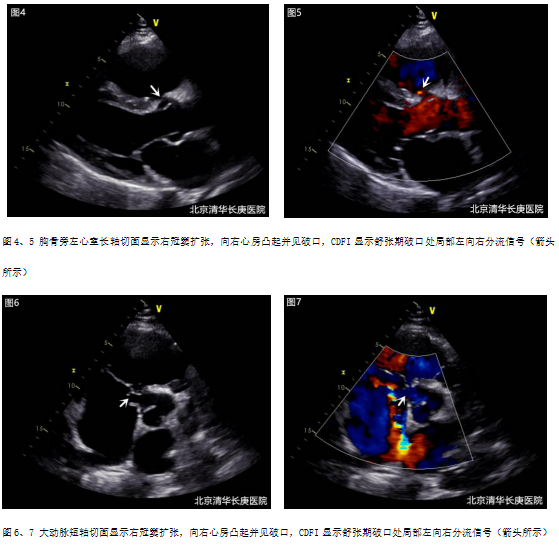

2. 超声心动图:

e.超声心动图提示主动脉右冠窦壁菲薄,呈囊袋样向右房膨出,基底部宽约9mm,顶端破口约6mm。

先天性心脏病 主动脉窦瘤破裂:心功能不全症状,近期诱因下加重,考虑窦瘤破裂;主动脉瓣听诊区连续性杂音;超声心动图提示主动脉右冠窦窦瘤破入右心房,故诊断较为明确。